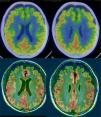

Dementia is a syndrome characterised by chronic, multi-domain, acquired cognitive impairment that causes significant functional limitations. MRI is the standard imaging study for these cases, since it enables detection of the atrophy patterns of the various neurodegenerative diseases (Alzheimer's disease, frontotemporal degeneration, Lewy body dementia), the vascular lesions associated with vascular dementia, and various potentially reversible diseases (for example, tumours, hydrocephaly) or diseases that require special management measures (for example, prion diseases). In certain cases other imaging methods can be used, such as CT, functional MRI, HMPAO SPECT or dopaminergic markers and FDG PET, amyloid markers or dopaminergic markers. The indications for these methods have not yet been clearly established, and therefore should be used in multidisciplinary dementia units.